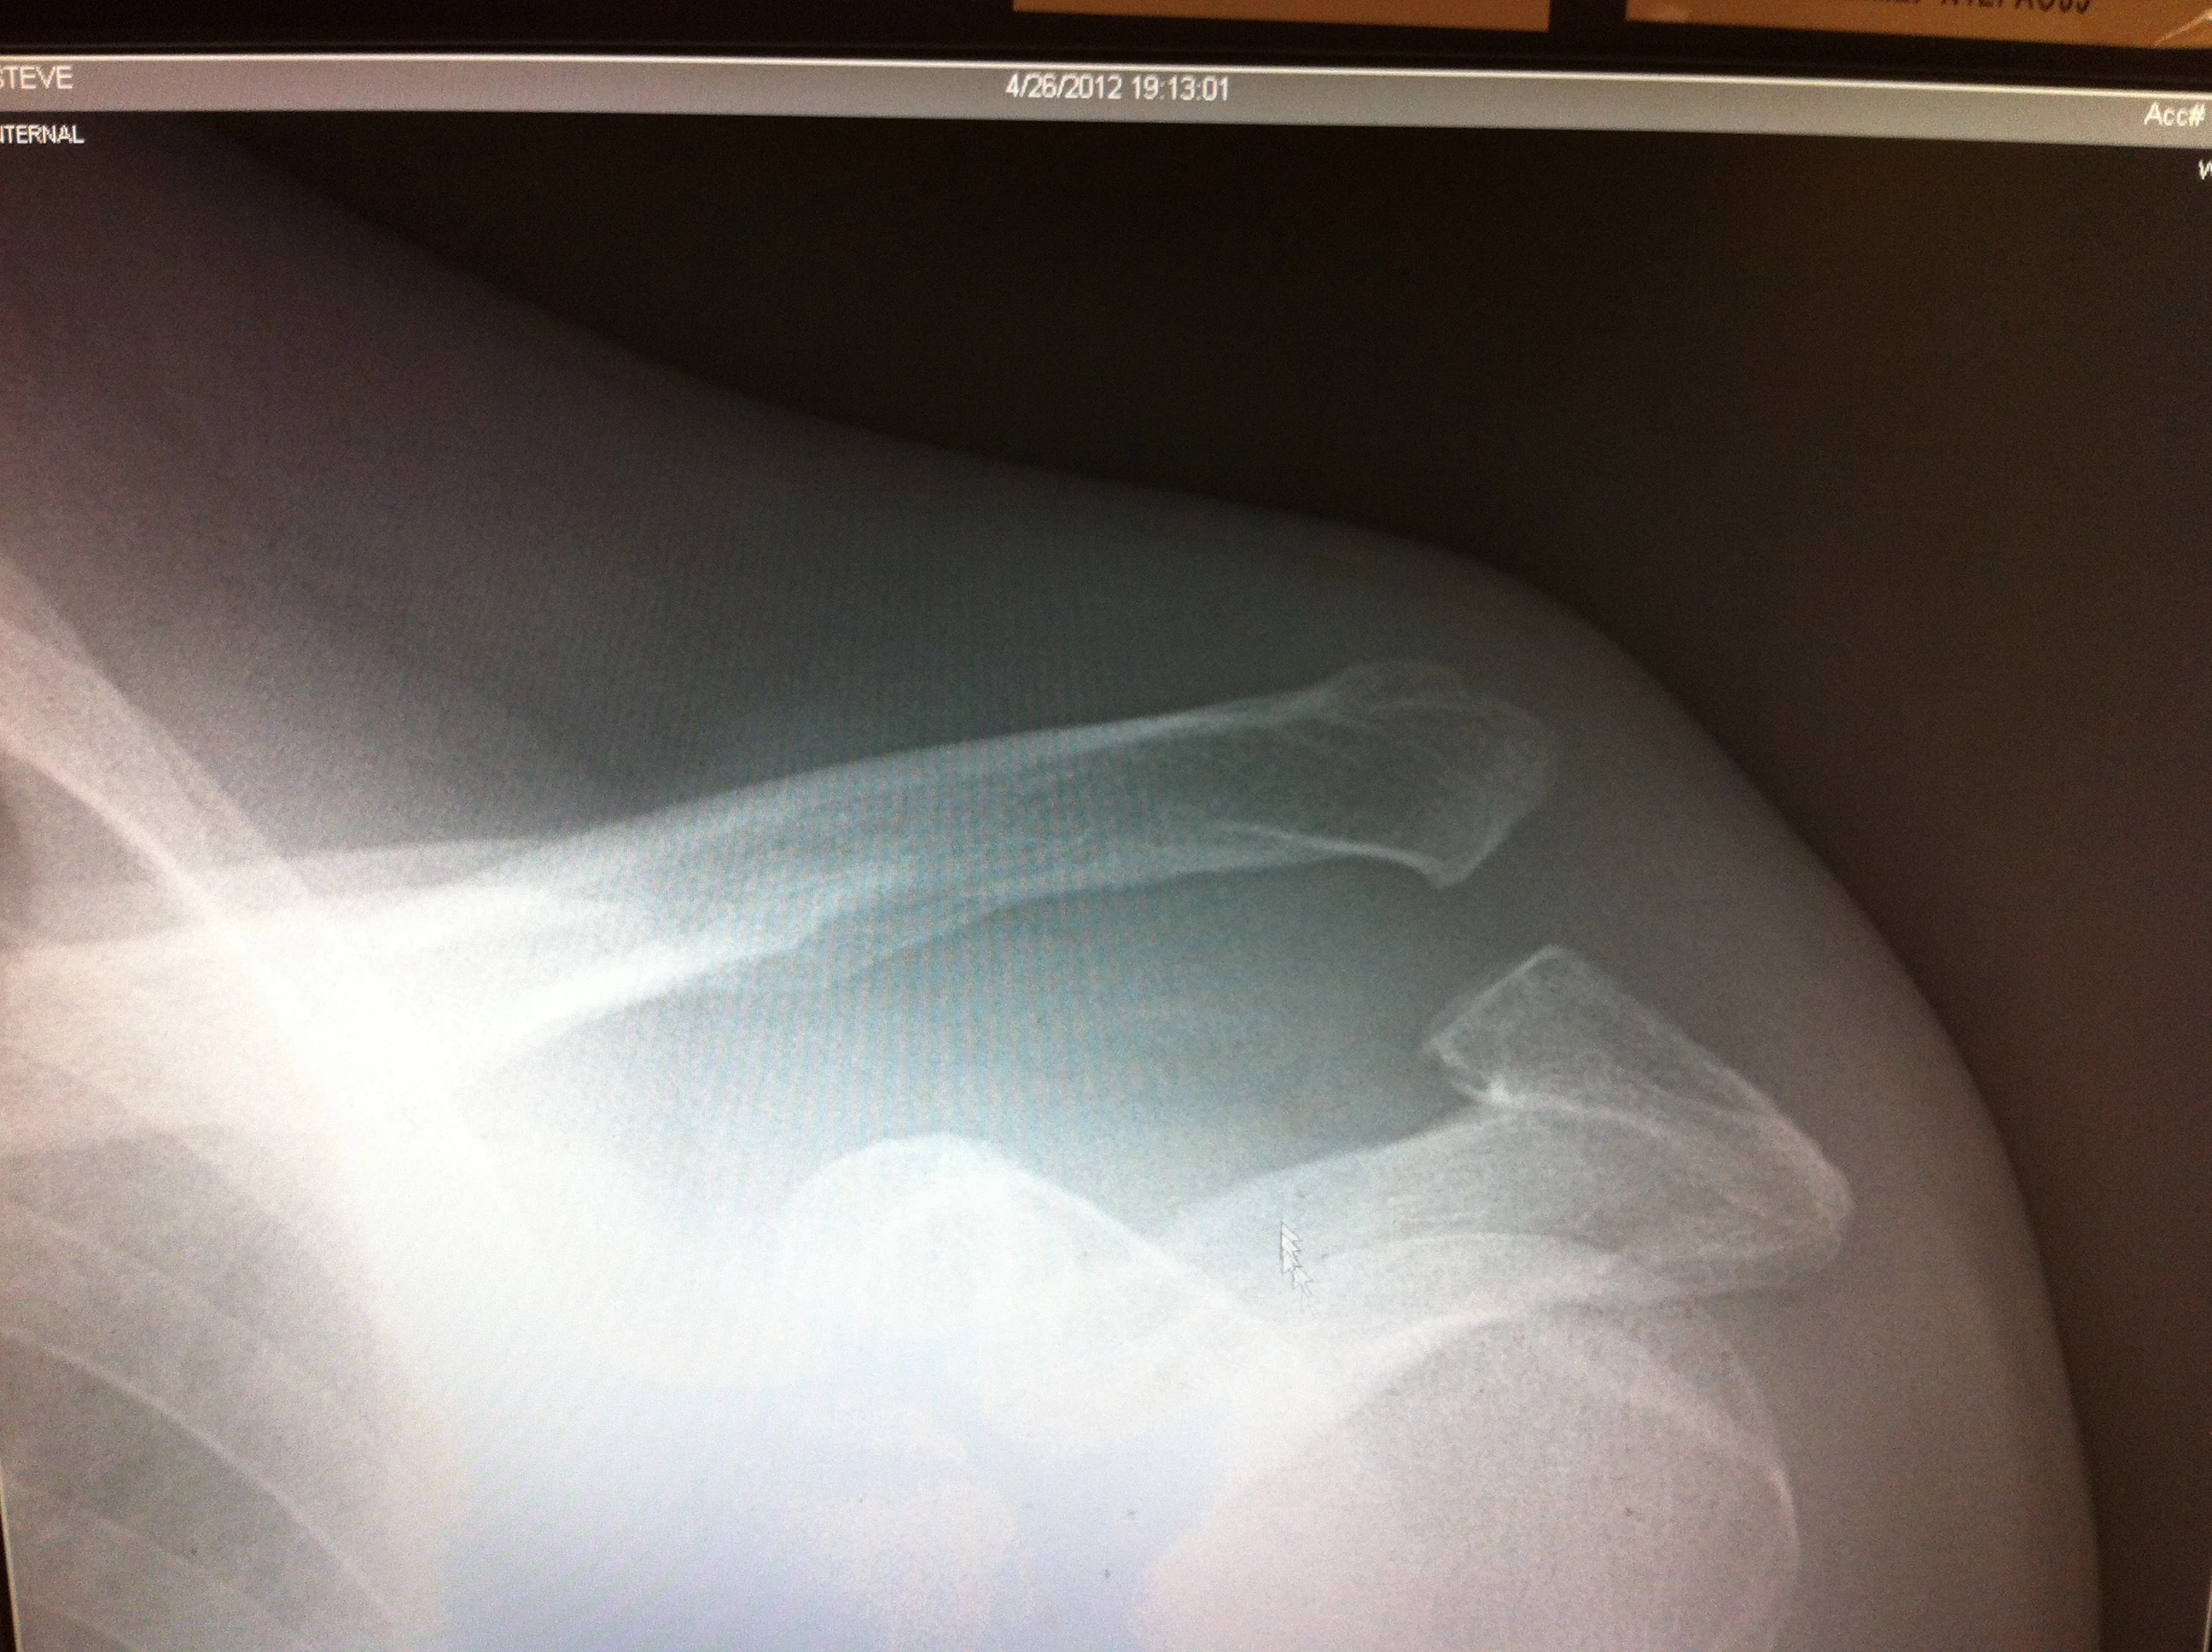

I have a cat 4 separation of my left shoulder. I haven’t had time to read up on it much, but the guy (doctor) said it was separated 2.5 centimeters and won’t heal itself and needs surgery. I don’t know about that.

I took this picture off the computer monitor. I’m not sure what I’m to look for that is important here, but it doesn

I’m not a docter, Steve, but I’ve separated my shoulder(s) a few times and I’d say your separation looks pretty severe. I would def. let your local doc/orthopedic examine your shoulder re: the potential for surgery. In the long run, you might be happier with getting it surgically repaired (and your shoulder working correctly) rather that dealing with chronic shoulder issues (like I do) for years and years.

Man…. So sorry that happened. We’re on the way up there this afternoon. The ER doc was right. Class 4 shoulder separation will NOT heal without surgery and not having a repair will eventually lead to atrophy of the ligaments and tendons within the joint. Not sure where you live…. John Conway in Ft Worth is an excellent surgeon who works with TCU and the Tx Rangers…. I’ve worked with him before and he also is a cyclist. He be a good guy to see if it’s convenient for you. Unfortunately, not all orthopedic surgeons are good at shoulders….. You need to ask around and be certain that they’re the best in the area. This is a must, or you’ll be sorry.

That x-ray reveals a severe should injury that in all likelihood can’t be resolved by time and PT. Those 2 bones on the right side should be together. They won’t heal like a broken bone will. Connective tissue has been seriously torn. I’ve been through this. Crash from front flat at 30, then rolled into path of car which rolled over my shoulder - miraculously not my head or torso. PT failed and over a year later I had surgery. Now I have 98% use of my shoulder, when with best result from the PT, I would have attained about 65%. My tearing was so bad that they had to use tissue from a cadaver to tie the collar bone back to the top of the shoulder blade. Like other guy said you don’t want to deal with the compromised shoulder for life or have to get the surgery over a year later. With that injury, this cycling season is down the tubes, but the sooner you are repaired the better. Sorry this happened to you. Sam W Columbia, MD PS - know the hill, did the race in 85 & 86 before I moved from MS to MD

From that radiograph you can’t really tell whether it is truly a Type 4 or 5 shoulder separation. Go see a good orthopedist to have it evaluated. Cyclists should be put together like dogs–no collarbone.